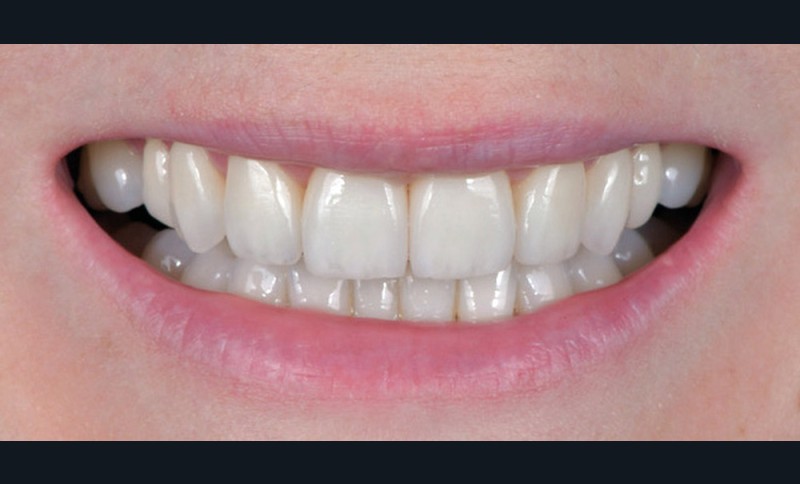

Les Drs Marie Clément et Clara Marcoux aborderont ensuite les différents apports de la dentisterie esthétique aux traitements orthodontiques. Les problèmes de dyschromies isolées ou généralisées, congénitales ou acquises seront développés ainsi que les anomalies de proportions dentaires (dents riziformes…), le maquillage (transformation d’une canine en incisive latérale…) et le remplacement des dents antérieures. Les auteurs présenteront l’intérêt du Digital Smile Design dans le diagnostic et la communication et l’arsenal thérapeutique à notre disposition pour améliorer la satisfaction de nos patients (éclaircissement, traitement des taches de l’émail, composites stratifiés, fig. 9a-d).